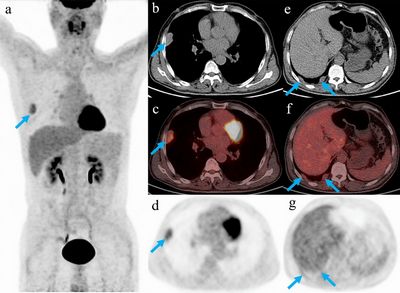

КТ стали важливим інструментом моніторингу ефективності лікування захворювань. КТ може допомогти медичним працівникам визначити, чи працює лікування, візуалізуючи зміни у внутрішніх структурах організму. Наприклад, якщо пацієнт проходить хіміотерапію для лікування раку, КТ можна використовувати для моніторингу розміру пухлини. Якщо пухлина зменшується, це означає, що лікування працює.

КТ-сканування використовують для оцінки лікування захворювань у різних медичних станах. Деякі з найпоширеніших захворювань, при яких використовується КТ, включають рак, серцево-судинні захворювання та неврологічні розлади. КТ може допомогти медичним працівникам визначити ефективність хіміотерапії або променевої терапії для лікування раку. Вони також можуть використовуватися для моніторингу прогресування серцево-судинних захворювань або ефективності лікування неврологічних розладів.

- Так, існує кілька альтернативних методів візуалізації, включаючи магнітно-резонансну томографію (МРТ) та позитронно-емісійну томографію (ПЕТ). Однак кожна методика візуалізації має свої переваги та обмеження, і вибір методу візуалізації залежить від захворювання, яке лікується, та методу лікування, який використовується.